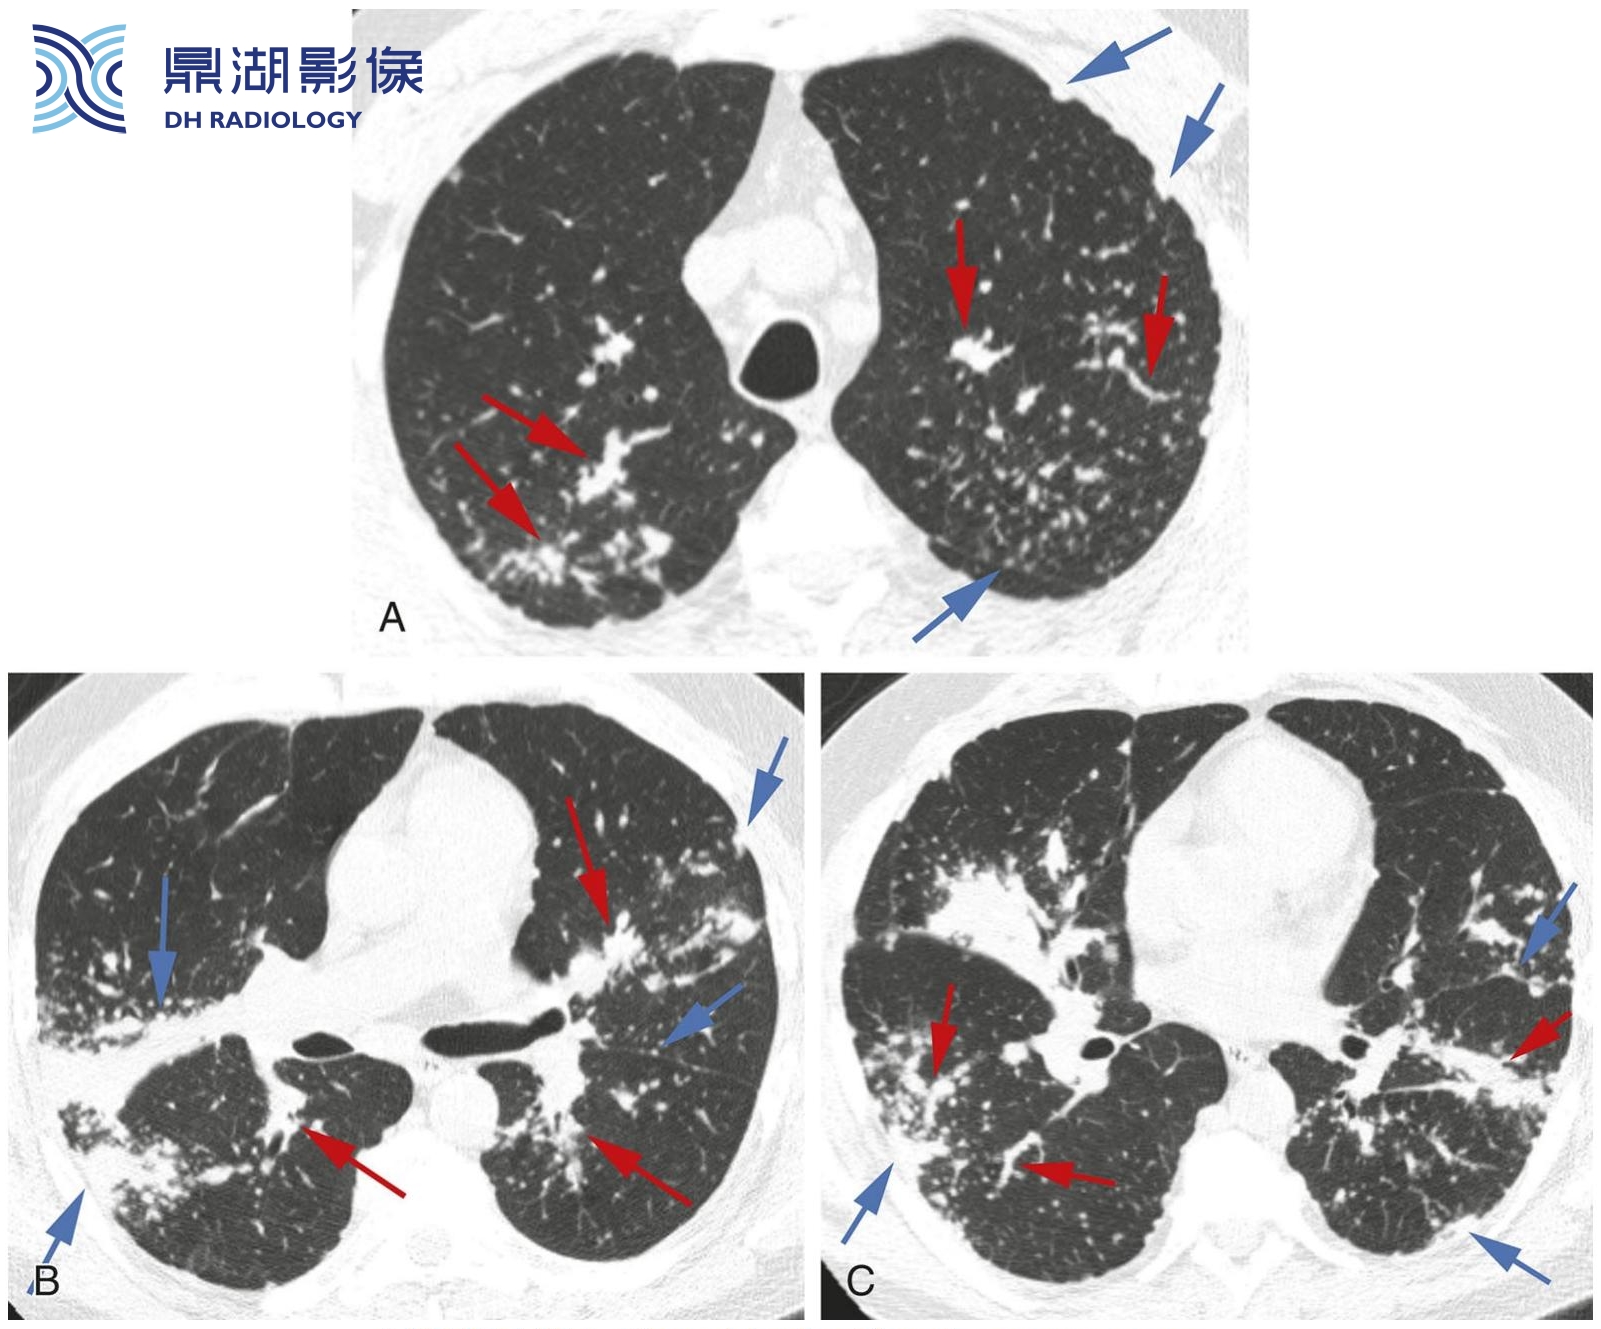

c02d9062cb233d985dc8bcd69eb92b1a.png

典型结节病伴支气管血管周围和胸膜下结节。

A.HRCT显示肺门区散在的结节,但是与上图相比,其与气管和支气管的关系较难确定。胸膜下结节清晰可见。

B.在较低的层面上,结节数量较少。结节主要分布在上叶,上叶分布是结节病的典型表现。